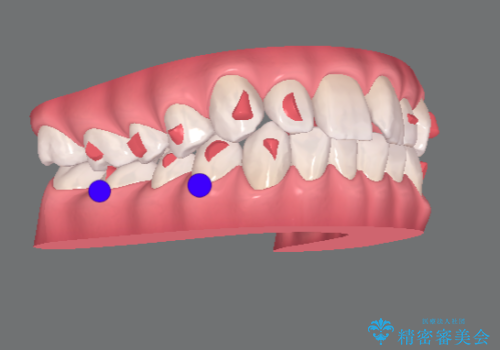

- インビザライン

- 出っ歯に見える前歯を治したい、と矯正治療を希望され来院されました。

奥歯の噛み合わせに大きな問題はないので、目立つ前歯の角度・隙間を重点的に整え、審美的な歯並びを獲得できるよう計画します。

治療によりしっかりと前歯の角度が改善され、審美的な歯並びを手に入れることができました。